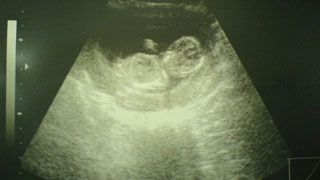

Премьер-министр Дмитрий Медведев подписал постановление о выделении субъектам РФ субсидий на проведение пренатальной (дородовой) диагностики нарушений развития ребенка в 2013 году. Согласно опубликованному документу, Саратовской области досталось 29,8 млн. рублей.

Размер субсидии каждого субъекта определен исходя из бюджетной обеспеченности региона и количества родов. Всего из федерального бюджета выделяется 850 млн. рублей.

Реализация распоряжения позволит проводить диагностику и выявлять врожденные или наследственные заболевания до рождения ребенка, оптимизировать медицинскую помощь женщине во время беременности, а также своевременно оказать плоду (внутриутробно) или новорожденному специализированную, в том числе высокотехнологичную, медицинскую помощь.